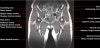

엉덩이 관절(고관절)의 MRI 단면 영상

- Checklist

1) Femur : Osteonecrosis, Fracture or Edema

2) Cartilage surface : Fissure, Fraying, Thinning or Defect

3) Joint recess : Chondral debris or Corpora aliena

4) Labrum : Tear, Detachment, Fraying or Degeneration

5) Acetabulum : Shallow contour?

6) Muscle and tendon : Tear or Strain

7) Trochanteric or Iliopsoas bursitis?

8) Check the symphysis pubis, superior/inferior pubic rami, ilium, sacroiliac joint and sacrum on large FOV coronal images